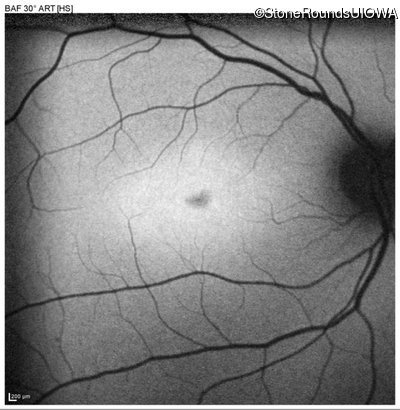

Blue Autofluorescence - Left - 20/125

Exemplar